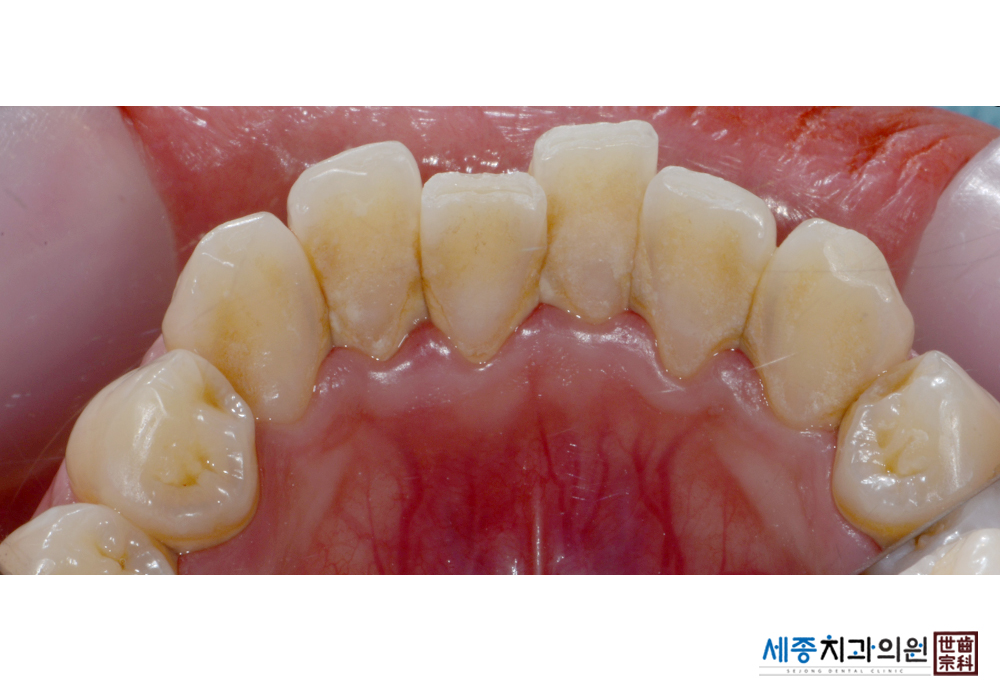

[스케일링] 치주질환 예방 스케일링 치료

치료후 : 2019-01-04

가글마취&저주파 스켈러를 사용한 스케일링